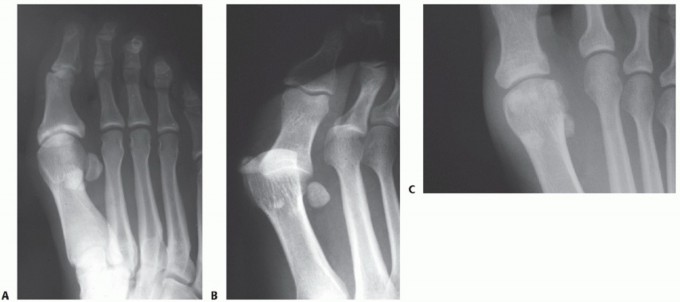

A thorough radiographic evaluation is mandatory (including weight-bearing views of the foot in the

anteroposterior [AP], lateral, and oblique planes) (FIG 3). Sesamoid axial views may also be helpful. Bilateral standing AP views are mandatory for comparison. Sesamoid station is assessed.

FIG 3 • A. AP foot radiograph showing proximal migration of the tibial sesamoid suggestive of an unstable turf toe injury. B. AP foot radiograph showing a hallux MP dislocation with an associated sesamoid fracture. C. AP radiograph demonstrating diastased bipartite tibial and fibular sesamoids. The proximal poles of each sesamoid are retracted.